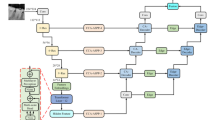

In clinical practice, accurate dental plaque segmentation plays an important role in the diagnosis of oral problems such as dental caries and periodontitis. Existing methods consistently exhibit undesired structural distortions owing to the intensive variations in shape and the ambiguous boundaries of the plaques. In this paper, we introduce a Structure-Preserving Dynamic Complementary Interaction Network (SPDINet) that facilitates complementary information interaction between main plaque segmentation sub-network and auxiliary boundary sub-network to address this problem. Mutual-attention module (MA) and gradient guided refinement module (GGR) achieve this dynamic interaction at the feature level and result level, so as to preserve perceptual-pleasant details and further avoid structural distortion for plaque segmentation. In MA module, A bi-directional cross-task Mutual-attention mechanism reduces misleading attentions and distributes attention responses to emphasize parts that one task overlook while another task highlights. In GGR module, gradient boundaries derived from mask prediction category-wisely refine the boundary probability map to generate a more accurate boundary around the object, which in turns significantly boosts the performance of segmentation and implicitly implements the information interaction. Experiments on two recent dental plaque segmentation datasets, including SDPSeg-S and SDPSeg-C, show SPDINet establishes new state-of-the-art results.